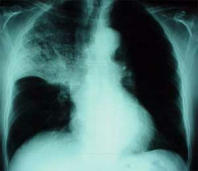

Pneumonia, x-ray photo

Blood group AB has - like blood group A - a chronic problem of mucus which provokes always a vulnerability for infection diseases: sinusitis, bronchitis, and pneumonia etc.

Example here is an x-ray photo with a pneumonia in the upper half of the right part of the lung.